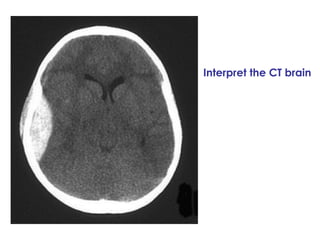

A 31-year-old woman was struck by a van and brought to the emergency department unconscious with a Glasgow Coma Scale of 5/15, a blood pressure of 240/130, and a heart rate of 58. She has unequal pupils with a dilated and non-reactive left pupil, indicating possible increased intracranial pressure from internal bleeding seen on CT scan, requiring burr holes to relieve pressure.